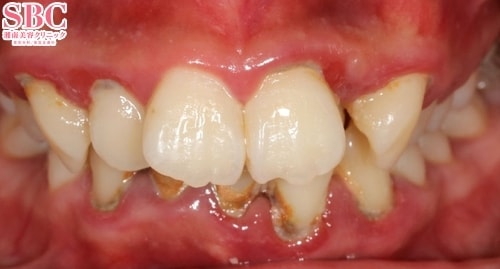

施術前

前歯が大きく捻れて生えておりました。また虫歯も発見!

上の歯8本をセラミックでキレイに!